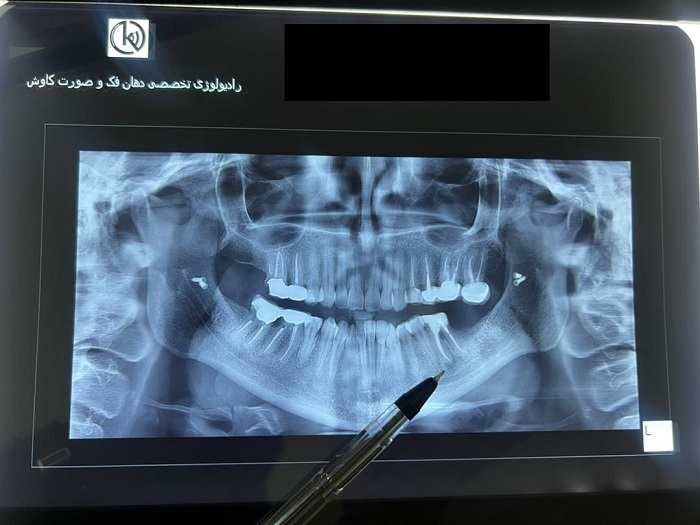

رادیوگرافی پانورامیک

یک رادیوگرافی پانورامیک دندان یک تصویر واحد می‌گیرد که دندان‌ها، استخوان‌های فک و ساختارهای اطراف صورت شما را نشان می‌ده...